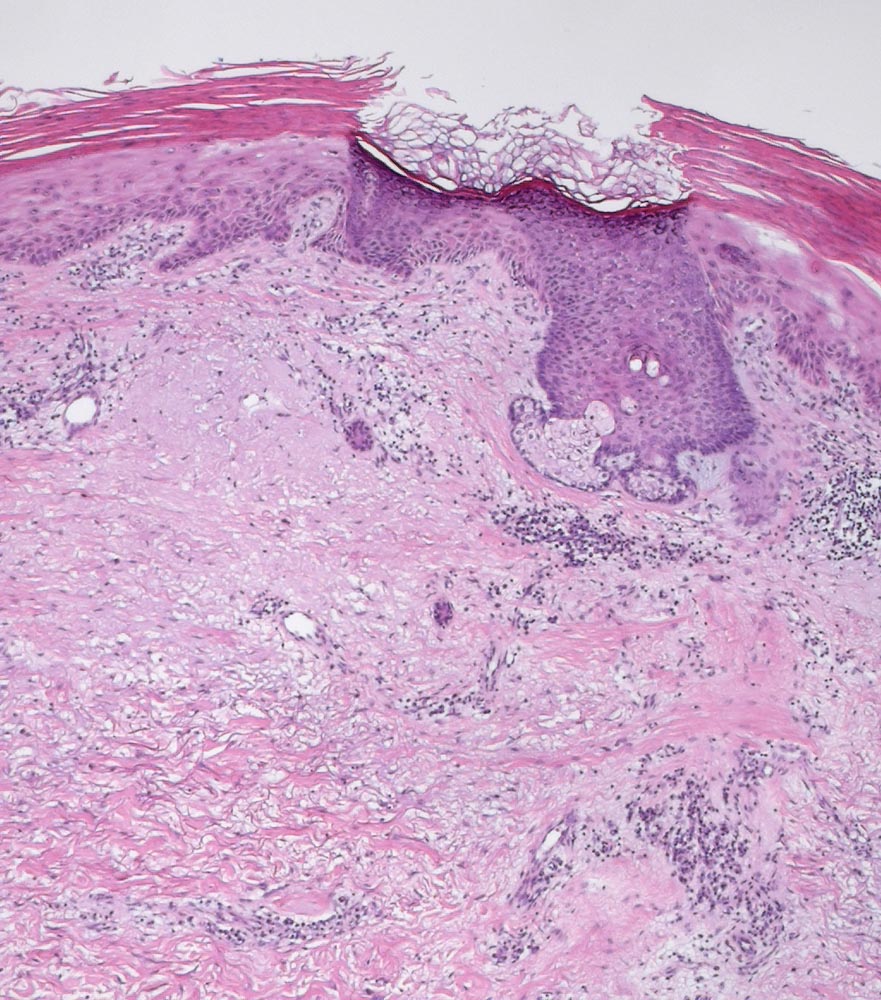

PathoPic – image database / PathoPic ID 10046 - Solare Präkanzerose (Keratose) mit leichter Epitheldysplasie

Solare Präkanzerose (Keratose) mit leichter Epitheldysplasie

Hyper-parakeratotisch verhornende akanthotisch verbreiterte Epidermis und schwere solare Elastose. Das dysplastische Epithel ist deutlich heller und zeigt eine gestörte Ausreifung. Die Keratinozyten haben vergrösserte atypische hyperchromatische Zellkerne. Sehr gut sichtbar ist hier die Aussparung der Hautadnexe. Das Epithel des Haarfollikels zeigt keine Dysplasie und die darüberliegende Epidermis zeigt eine normale korbgeflechtartige Verhornung.

Nachexzisat nach Exzision eines atypischen Fibroxanthoms an der Stirn.